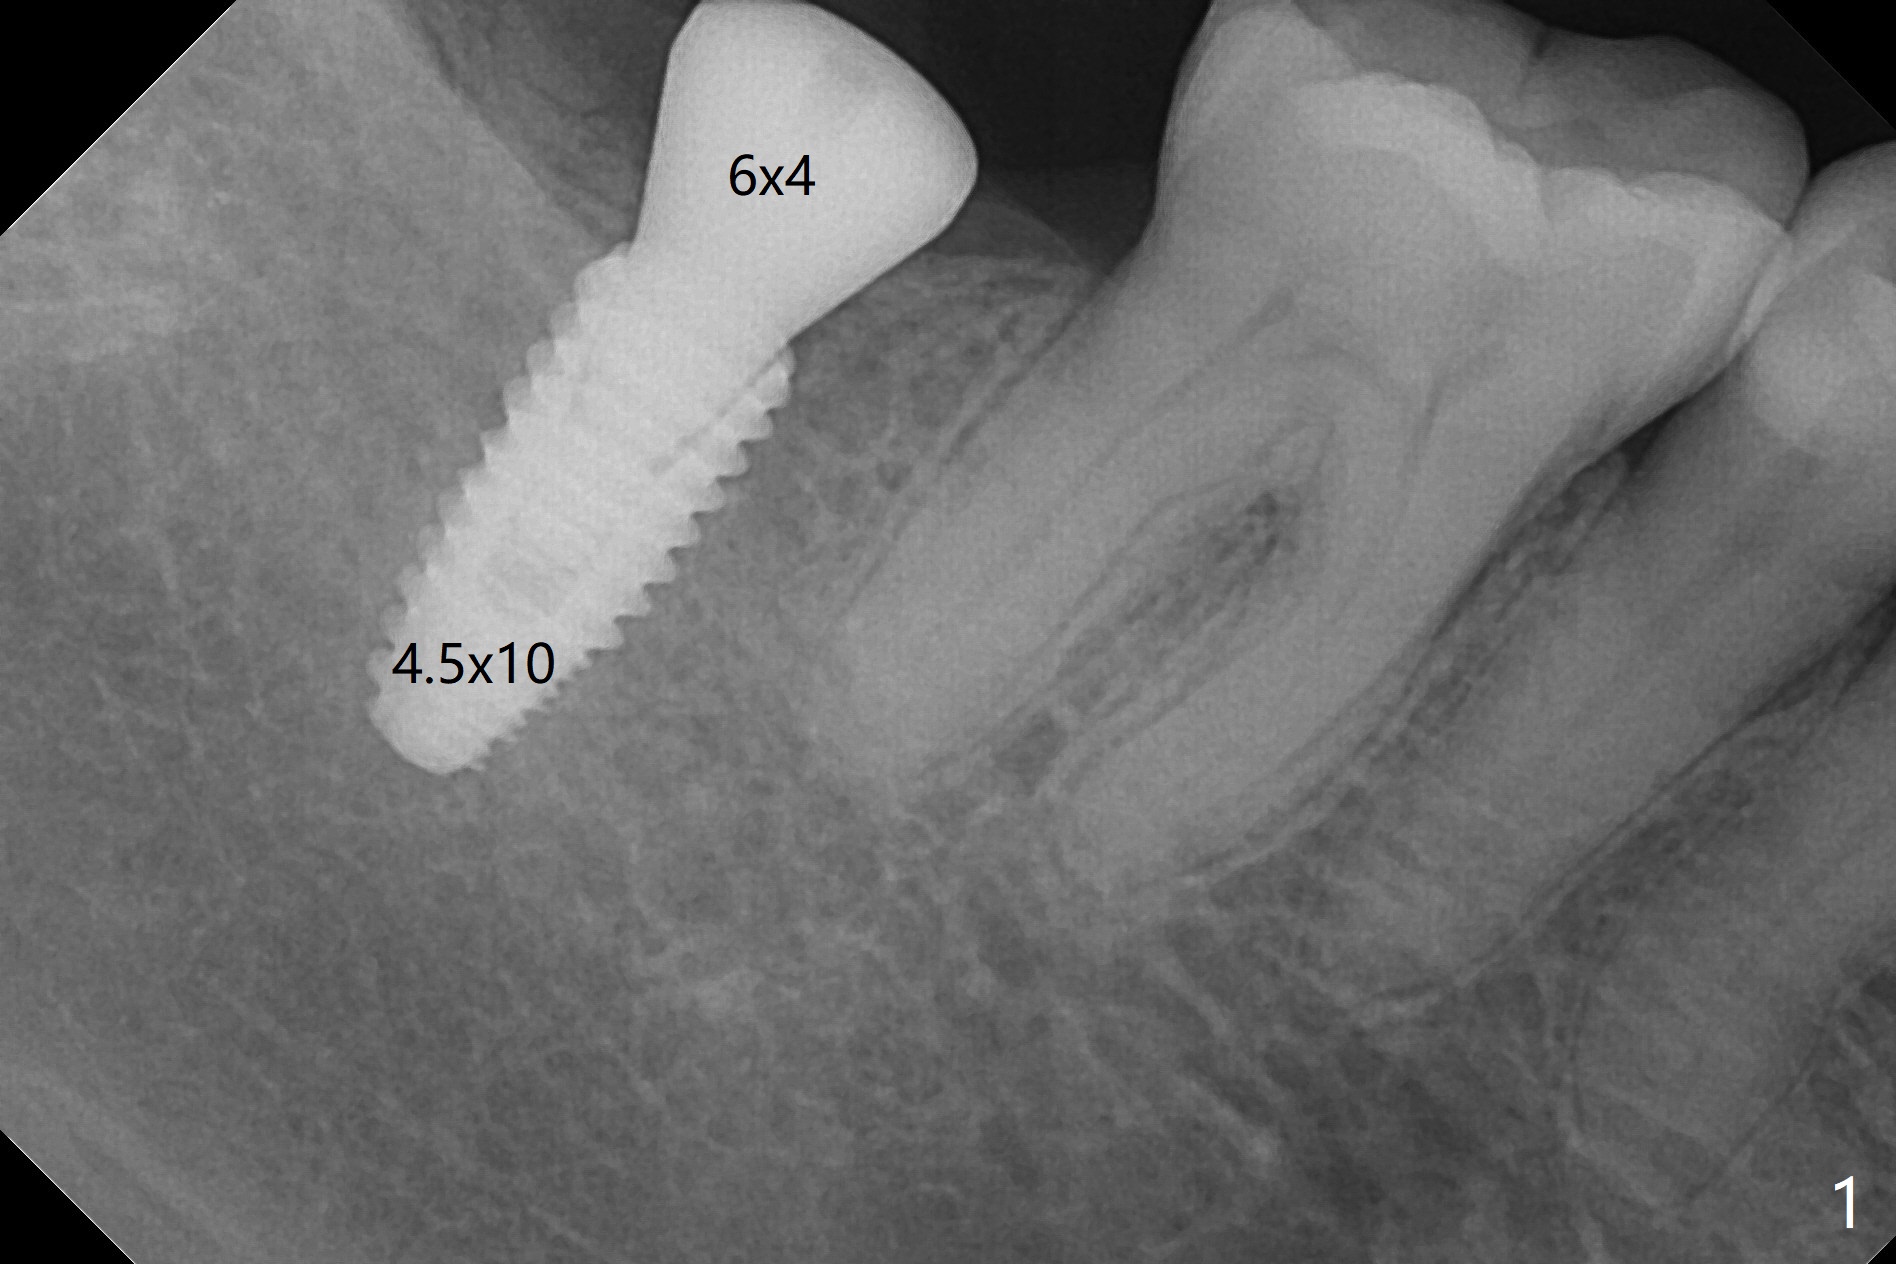

After placement of a 4.5x10 mm implant with guide at #31 and before placement of a 6x4 (Fig.1) and finally a 5.5x4 (Fig.2) mm healing abutment, a 5.7x5(2) mm dummy (planning) abutment is placed without restorative space. It appears that either orthodontic or restorative intrusion is necessary. The patient prefers the latter. The reasons of switching the large healing abutment to the smaller one are two-folded. The primary stability of the implant is ~ 10 Ncm. Tongue mobility may cause fibrointegration. The 6 mm abutment seems to contact the mesial crestal bone (Fig.1). In fact the smaller abutment does not help much. It may be related to radiation angulation. A smaller sensor will be used to reduce the angulation 3-4 months later. In fact #1 sensor does produce better image with less angulation (Fig.3). After trimming a 5.2x4.5(3) mm abutment and opposing tooth (palatal cusp), impression is taken.